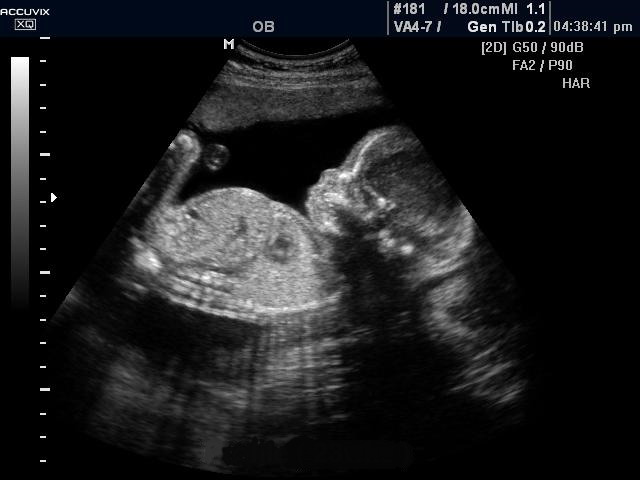

Фото УЗИ ребенка на 21-22 неделе беременности

Фото УЗИ ребенка на 10 неделе беременности . оценка динамики развития и набора веса . Фото УЗИ ребенка на 21- 22 неделе беременности . Визуально во время ультразвуковой диагностики заметно увеличение размеров плода .